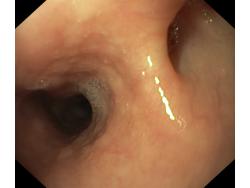

Uchyłki